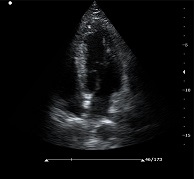

? ? ? ?C7為深圳安盛生物醫(yī)療技術(shù)有限公司新一代便攜式彩超產(chǎn)品,采用了先進(jìn)的PC平臺(tái),擁有強(qiáng)大的處理能力,優(yōu)異的圖像性能,集小巧輕便、全面的功能與輕巧流暢、特有的U型設(shè)計(jì)與一身,提供大眾新選擇。

? ?● 多種成像模式

? ? ? ?B、C、PW、CW、BCD三功、大角度偏轉(zhuǎn)成像、實(shí)時(shí)寬景成像、梯形成像(僅支持線陣)、解剖M型、彩色M型成像、組織多普勒成像、3D/4D成像